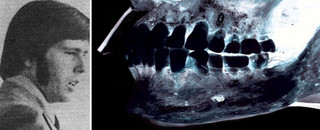

Η κολοσσιαία ερευνητική πρωτοπορία της συγκεκριμένης υπόθεσης ήταν η φωτογραφική υπέρθεση (superimposition) των κρανιοεγκεφαλικών χαρακτηριστικών της κεφαλής που βρέθηκε στο δέμα και μιας φωτογραφίας της συζύγου του γιατρού, με τα δυο κεφάλια να ταιριάζουν απόλυτα! Με την ίδια τεχνική, ταυτοποιήθηκε και το δεύτερο θύμα, που ήταν η οικονόμος της Ισαμπέλα Κερ-Ράξτον. Ο γιατρός σκότωσε τη γυναίκα του σε ένα ξέσπασμα βίας και κατόπιν ξέκανε και τη βοηθό της για να καλύψει τα ίχνη του…